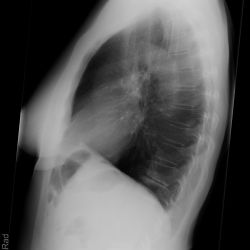

Chilaiditisyndrom